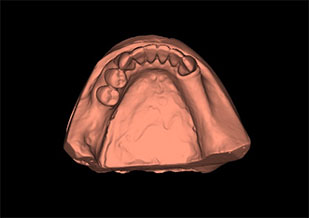

Digitalización de modelos e impresiones 3D.

De gran utilidad en ortodoncia, permite almacenar todos los modelos en formato digital. El paciente puede observar la evolución de su casa en 3D.